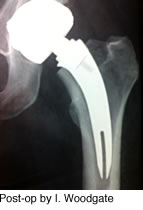

Evaluations of instrumentation, trial stems and final implants have been carried out successfully.

Design and technique have provided for a simple stem design (five sizes) with novel features that offer significant implant-to-bone stability, ease of surgical approach, reproducible techniques, and impressive short term clinical outcomes.